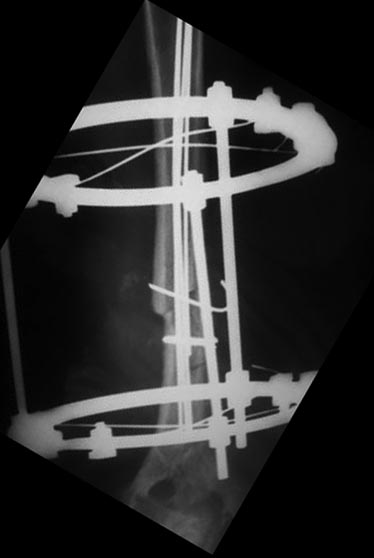

Уважаемые коллеги, прошу прощения за задержку ответа. Операцию проводили

27.11.13г по настоятельной просьбе докторов там, где был оперирован,

поэтому пришлось долго ждать контроль.Р-грамму и самого больного, только

сегодня приехали. Операция более 4 часов, во время операции установлено

полное повреждение лучевого нерва, концы булавовидно утолщены, дефект

2,5-см, с трудом и очень долго пришлось мобилизовать, частично был

замурован костной мозолью . Кость укорочена на 3 см, пластика типа

русского замка, в это время часть дистального отломка откололась,

поэтому пришлось фиксировать винтом, и еще косо спицей., и/м 4-мя

спицами, шов нерва, под нервом слой мышца, АВФ из двух колец с

компрессией. Р-снимки прилагаются.